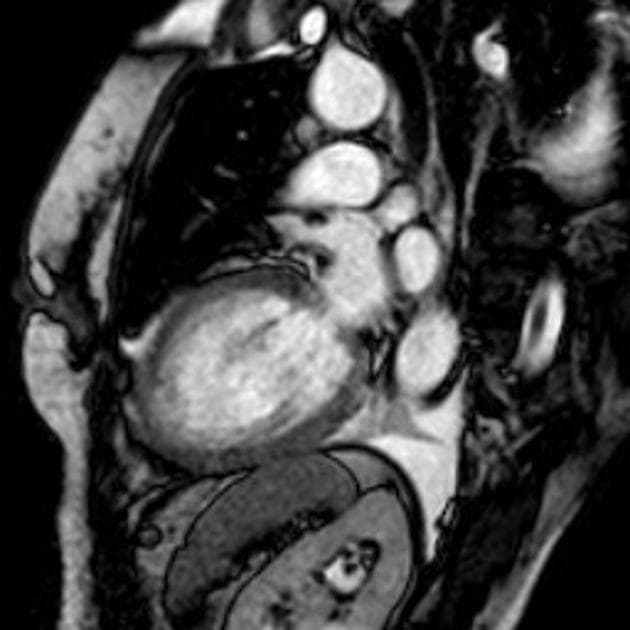

- Không thấy hình ảnh (no evidence of) vỡ thất, nhưng hình ảnh động (cine images) cho thấy thành trước giữa thất trái bị rối loạn vận động (dyskinetic), phồng ra ngoài trong thì tâm thu.

- Trên hình STIR, đoạn cơ tim tổn thương tăng tín hiệu (hyperintense), phù hợp với phù (edema).

- Có tràn dịch màng ngoài tim lượng nhỏ (small pericardial effusion).

- Vị trí tổn thương là bất thường, vì thường thì các đoạn đỉnh (apical segments) bị ảnh hưởng trong bệnh lý này. Tuy nhiên, ba kiểu hình ảnh khác biệt đã được ghi nhận: hai thất (biventricular), giữa thất (mid-ventricular – như trường hợp này), và đoạn đáy (basal).

- Trên cộng hưởng từ (MRI), các phát hiện điển hình gồm phù cơ tim (myocardial edema) và không có thiếu máu cục bộ (ischemia) hay xơ hóa (fibrosis), điều này được chứng minh bằng việc không tăng quang ở thì muộn sau tiêm gadolinium (lack of enhancement at late gadolinium imaging).

Bệnh cơ tim Takotsubo, còn gọi là bệnh cơ tim do stress, đặc trưng bởi rối loạn chức năng thất trái tạm thời do stress về mặt cảm xúc hoặc thể chất, thường gặp ở phụ nữ sau mãn kinh. Mặc dù thể 'phình đỉnh' cổ điển là phổ biến nhất, các thể bất thường như thể giữa thất, thể đáy và thể hai thất ngày càng được nhận biết rõ. Trường hợp này biểu hiện thể giữa thất với rối loạn vận động của thành trước giữa và phù cơ tim trên cộng hưởng từ, nhưng không có dấu hiệu nhồi máu hay xơ hóa. Việc không thấy tăng quang muộn là điểm phân biệt quan trọng với tổn thương do thiếu máu. Diễn tiến lâm sàng với cải thiện tự phát trong vài tuần khẳng định chẩn đoán. Nhận biết các biểu hiện bất thường này là rất quan trọng để tránh chẩn đoán nhầm thành hội chứng vành cấp.